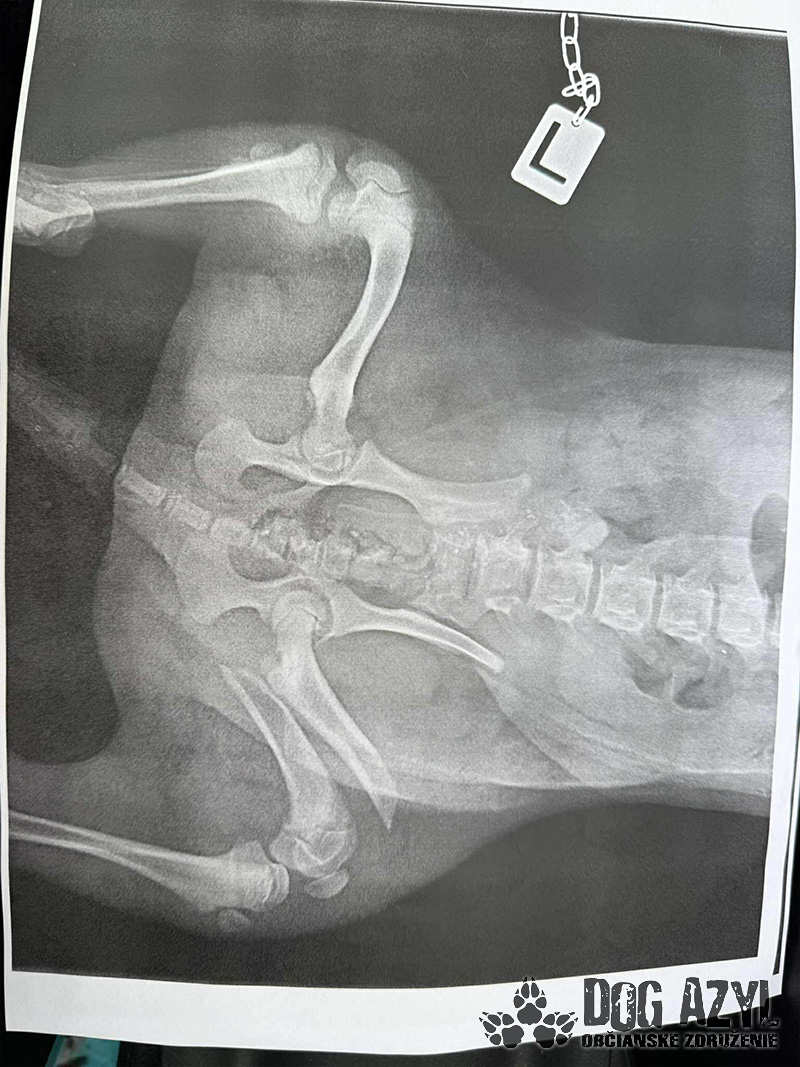

Drobec, ktorý medzičasom dostal meno Gerro, sa napriek všetkému celý čas tešil ľudskej pozornosti a krútil chvostíkom. Má veľmi škaredé zlomeniny prednej aj zadnej labky, pomliaždeniny na celom telíčku, ale našťastie lebka a chrbtica by mali byť v poriadku. Naše srdcia sú z tohto prípadu dolámané tiež na milión kusov, modlíme sa a veríme, že operácie zvládne! My budeme pri ňom a pomôžeme mu vo všetkom, v čom len bude treba.

Momentálne je hospitalizovaný u nášho veterinára, kde ho včera pripravovali na náročné operácie, ktoré by podľa plánov mal podstúpiť dnes. Čaká ho ešte veľmi dlhá cesta, ale pomôžeme mu zvládnuť každý jeden krôčik!